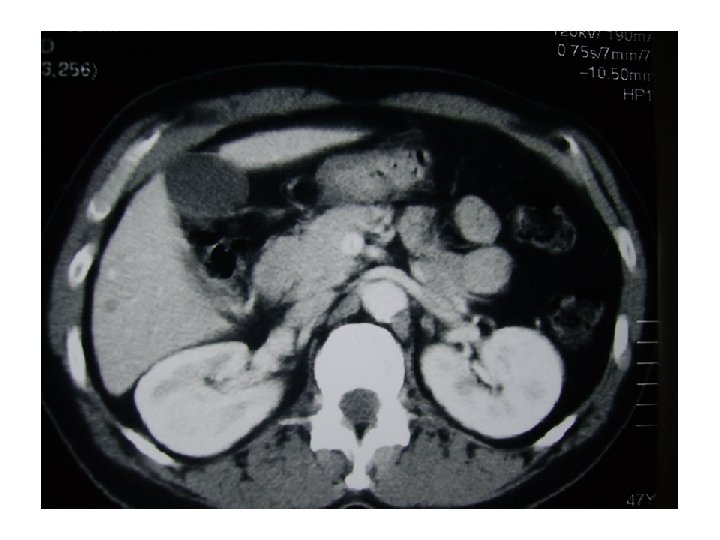

Exploraciones Rx de tórax: ocupación del seno costodiafragmático (¿derrame pleural? ) y masa hiliar derecha con elevación diafragmática homolateral. TAC tóraco-abdominal: gran masa mediastínica hiliar derecha (64 mm x 40 mm); amputación del bronquio principal derecho y afectación de la carina y tráquea en su tercio distal, con ocupación del bronquio lobar superior derecho y colapso completo del lóbulo medio e inferior derecho. La masa infiltra vena cava superior y arteria pulmonar. Se detectan adenopatías subcarinales y paratraqueales superiores e inferiores derechas de 16 a 25 mm, así como infiltrados periféricos en lóbulo superior derecho. En hígado hay tres nódulos hipodensos (segmento II y VI) de 7, 30 y 5 mm respectivamente, de significado incierto. La fibrobroncoscopia objetivó una tumoración que obstruía casi completamente el bronquio intermediario. El estudio histológico fue de adenocarcinoma pobremente diferenciado. El estudio de marcadores genéticos detecta una amplificación (FISS) del EGFr sin mutaciones y una sobre-expresión (en el rango superior de la normalidad) del BRAC 1.